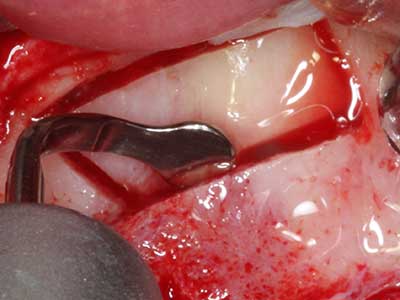

Bone tissue is not simply a mineral structure but also contains a substantial proportion of collagen fibres. This means it not only has good compressive strength but also a degree of flexibility, which can be taken advantage of when performing bone augmentations. In the classical expansion procedure using bone splitting, the atrophied alveolar ridge is split longitudinally and carefully expanded after reaching an adequate osteotomy depth (Fig. 13-16), ideally without substantial removal of the periosteum (Brugnami, Caiazzo et al. 2014, Stricker, Fleiner et al. 2014). Screw and plate systems with increasing expansion distance have proven effective in separating the two bone lamellae while remaining below the fracture threshold. In general, residual bone widths of at least 3–4 mm are required (Chiapasco, Zaniboni et al. 2006) to guarantee adequate flexibility and sufficient bone coverage of the future implants. If necessary, a vertical relief osteotomy on one or both sides can improve flexibility. A combination with additional augmentation techniques, particularly on the buccal side, has been described as an alternative to the classical technique.